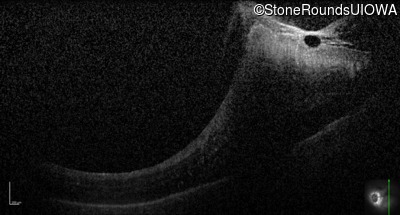

Optical Coherence Tomography - Right - 20/50 -3

Exemplar / OCT Stack